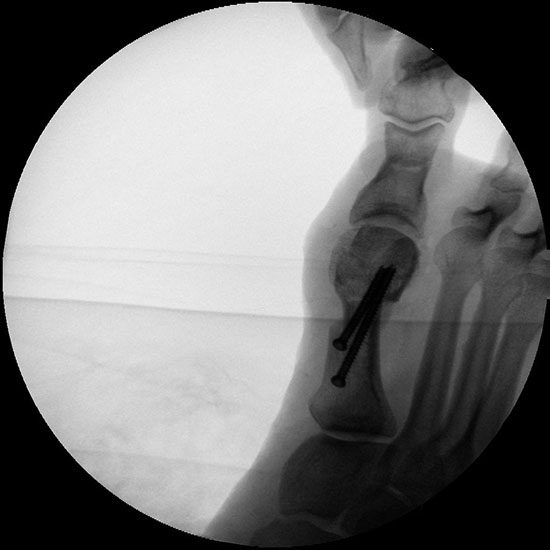

Abbildung 32

Bei entsprechender Wahl der Osteotomieebene kann auch bei minimalinvasiver Chevron-Osteotomie eine deutliche Plantarisierung des Metatarsalekopfes erreicht werden.